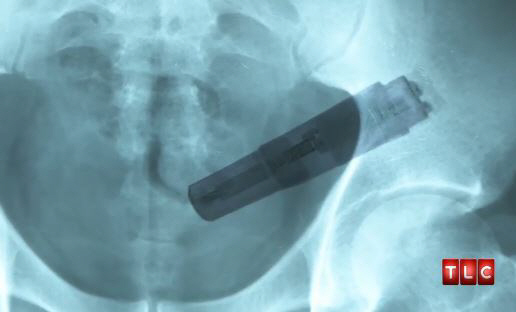

결국 병원측이 엑스레이 촬영을 하면서 남성의 몸을 떨게 한 원인을 찾았다. 그것은 다름아닌 여전히 작동중인 자위기구였던 것.

포프는 "환자에게 즉시 기구를 제거하지 않으면 내부 출혈이나 감염 등의 심각한 상황을 불러 올 수 있다고 전했다"며 "치료후 자위기구인 바이브레이터가 어떻게 대장속에 들어갔는지 물었지만 그는 끝내 답변을 거부했다"고 말했다.

| 자위기구가 대장속에 박힌 남성. 사진캡처=TLC 방송 |